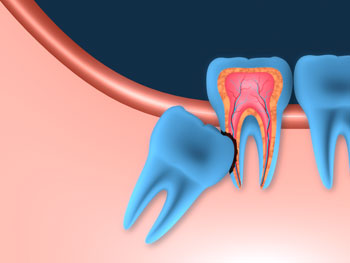

Wisdom teeth (or third molars) are the last four teeth to erupt and generally come in during the late teen years or early twenties. The jaw is often too small to accommodate the new wisdom teeth comfortably, so their eruption often causes pain and requires removal.

At your consultation, your Smile dentist will advise whether your wisdom teeth are fine or likely to cause problems. If your wisdom teeth are likely to be problematic, your dentist may recommend a surgical extraction.

Your dentist will use local anaesthesia, sedation or general anaesthesia in order to numb your mouth and/or suppress your consciousness during the surgery. An incision will then be made in the gum to expose the tooth and bone. If any bone is blocking access to the root of the tooth, it will be removed. If the tooth is difficult to remove, it may be divided into several pieces before being removed. After that, the extraction site is cleaned and any remaining debris is removed. The site is stitched up if required for healing before gauze is placed over the site to control any bleeding and assist the formation of a blood clot.

If your wisdom tooth is impacted, saliva, bacteria and food can accumulate around it. This causes decay to the wisdom tooth or the tooth beside it. This often leads to a painful infection.

Gum Infection

Pressure Pain

Cyst Formation